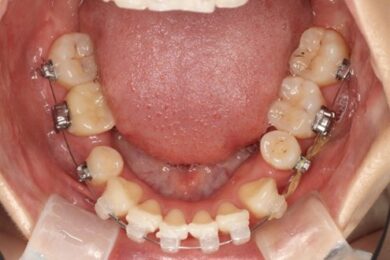

下顎のビフォアアフター

2か月前 現在

下顎の方は重なりが解けるよう、一本一本並ぶように全体的に動いてきています。

臼歯の内側に倒れていたところも起きてきて上を向くようになってきています。

今までは抜歯したところを中心にパワーチェーンをつけていましたが、今回の調整からはパワーチェーンを全体につけ奥(後ろ)に下げていきます。全体の重なりをなくしていきます。